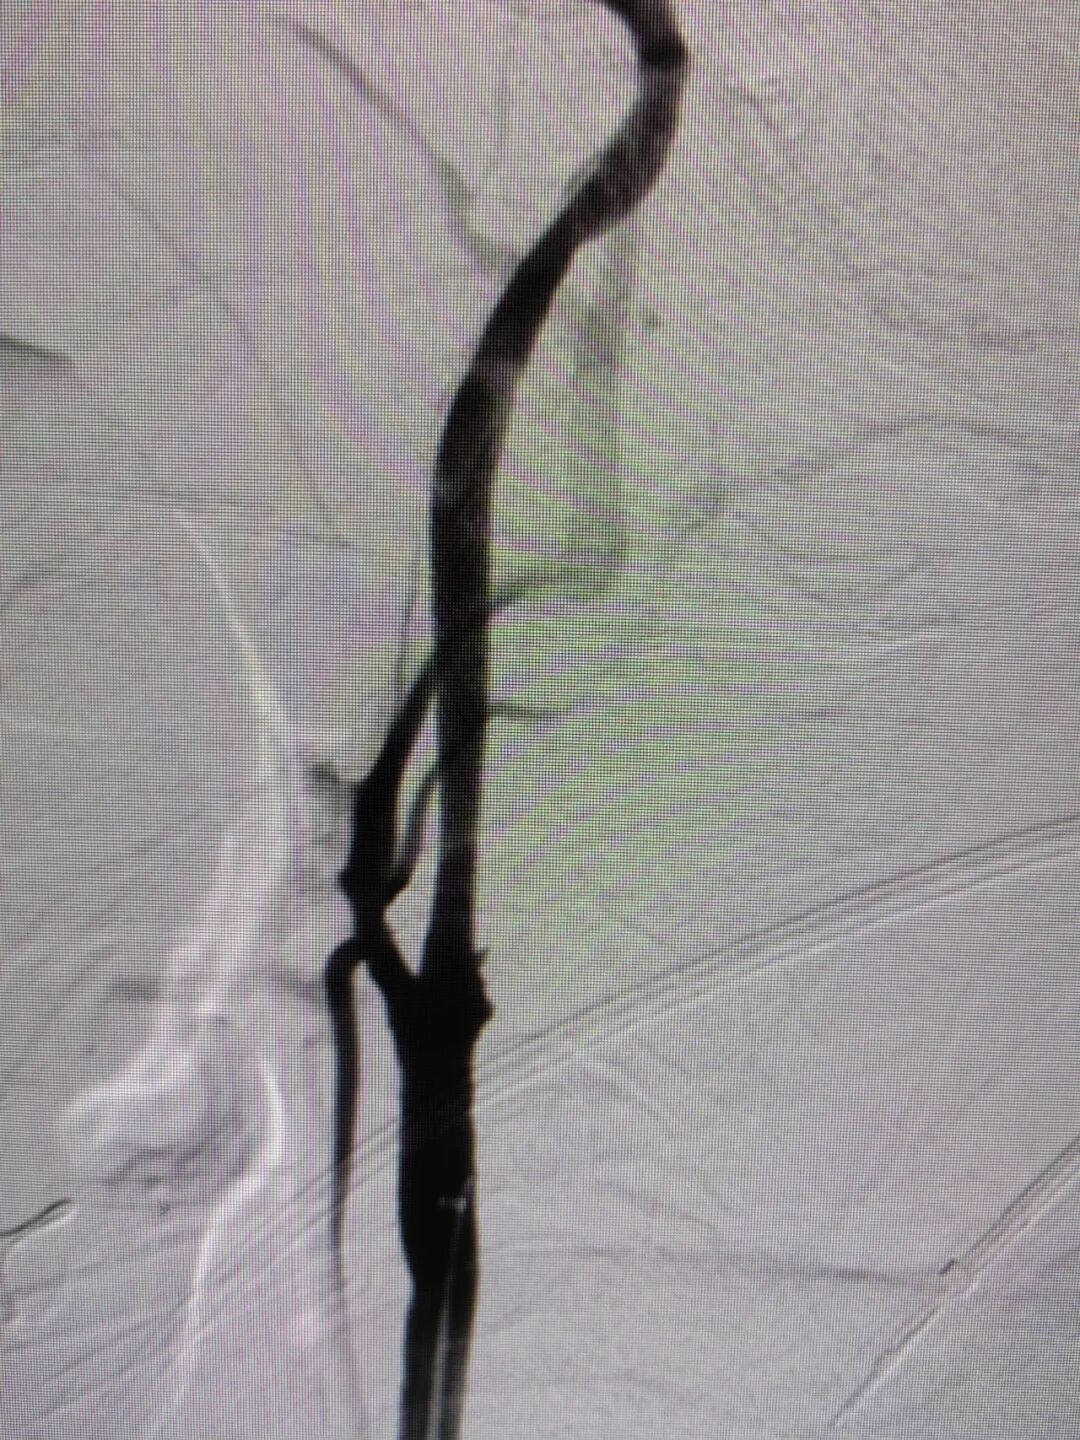

手术过程

经右侧桡动脉穿刺置入7F 薄壁鞘,畅医达 Calvada 5F 内腔0.072'' 导管鞘同轴125cm 5F 西蒙Ⅱ导管,在0.035'' 导丝引导下顺利到达右侧颈总动脉远端,小球囊预扩后,送入5mm 保护伞,4.0mm×30mm 球囊扩张后置入7mm×40mm 颈动脉支架。